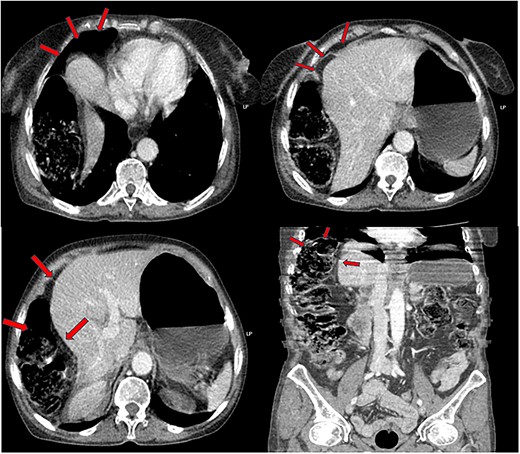

We decided to complete our investigation by performing a contrast enhanced abdominal CT-scan. The result of which showed an interposition of the right colon between the liver and diaphragm, with circumferential thickening of the sigmoid colon, suggestive of an inflammatory or infectious nature, without pneumoperitoneum (Fig. 2).

Interposition of the right colic angle and a part of the ascending colon, between the right diaphragm and the liver (image of pseudo-pneumoperitoneum).